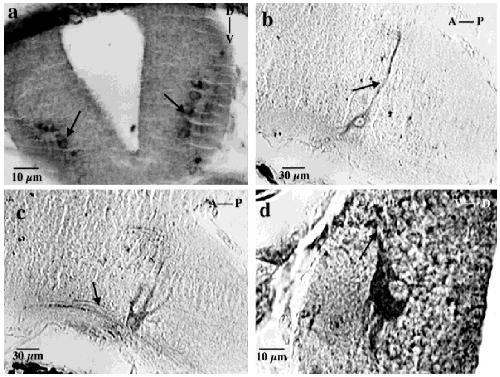

Interleukin-1beta and its type 1 receptor are expressed in developing neural circuits in the frog, Xenopus laevis., J Comp Neurol 1998 |